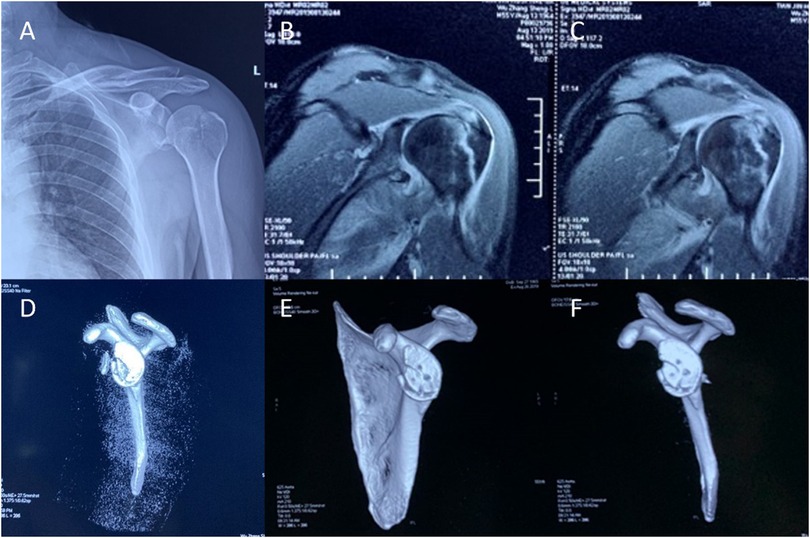

Radiographic and MRI evaluation identified a nondisplaced fracture of the left greater tuberosity (Figure 1A) and a fracture involving the anteroinferior glenoid rim with associated labral involvement (Figures 1B,C). MRI additionally revealed a partial tear of the supraspinatus tendon. CT confirmed the greater tuberosity fracture and demonstrated a comminuted anteroinferior glenoid fracture (Figure 1D). Preoperatively, the patient's pain score was 9 on the Visual Analog Scale (VAS scale), with a Constant-Murley Score (Constant score) of 33 and an American Shoulder and Elbow Surgeons Standardized Shoulder Assessment (ASES score) of 13.

CT at 6 months demonstrated satisfactory alignment and healing of the glenohumeral fracture (Figures 1E,F). At 15-month follow-up, the patient reported complete resolution of shoulder pain, with restored range of motion. Clinical scores were markedly improved: VAS 0, Constant score 95, and ASES score 94. Imaging confirmed postoperative healing changes in the left glenoid fossa fracture—with good bone repair and a relatively regular shape.